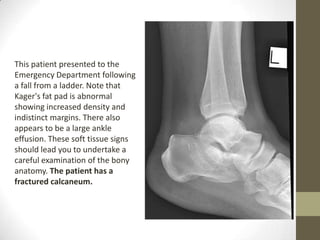

This patient presented to the

Emergency Department following

a fall from a ladder. Note that

Kager's fat pad is abnormal

showing increased density and

indistinct margins. There also

appears to be a large ankle

effusion. These soft tissue signs

should lead you to undertake a

careful examination of the bony

anatomy. The patient has a

fractured calcaneum.